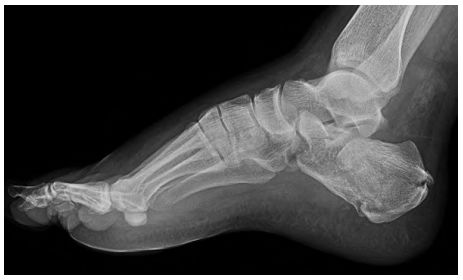

54 跟骨骨折矯正復位時,跟骨結節關節角(Bohler’s Angle)的矯正對足踝功能很重要。下圖之跟骨骨折, 理想之跟骨結節關節角矯正後約幾度? (A)5 (B)10 (C)40 (D)80